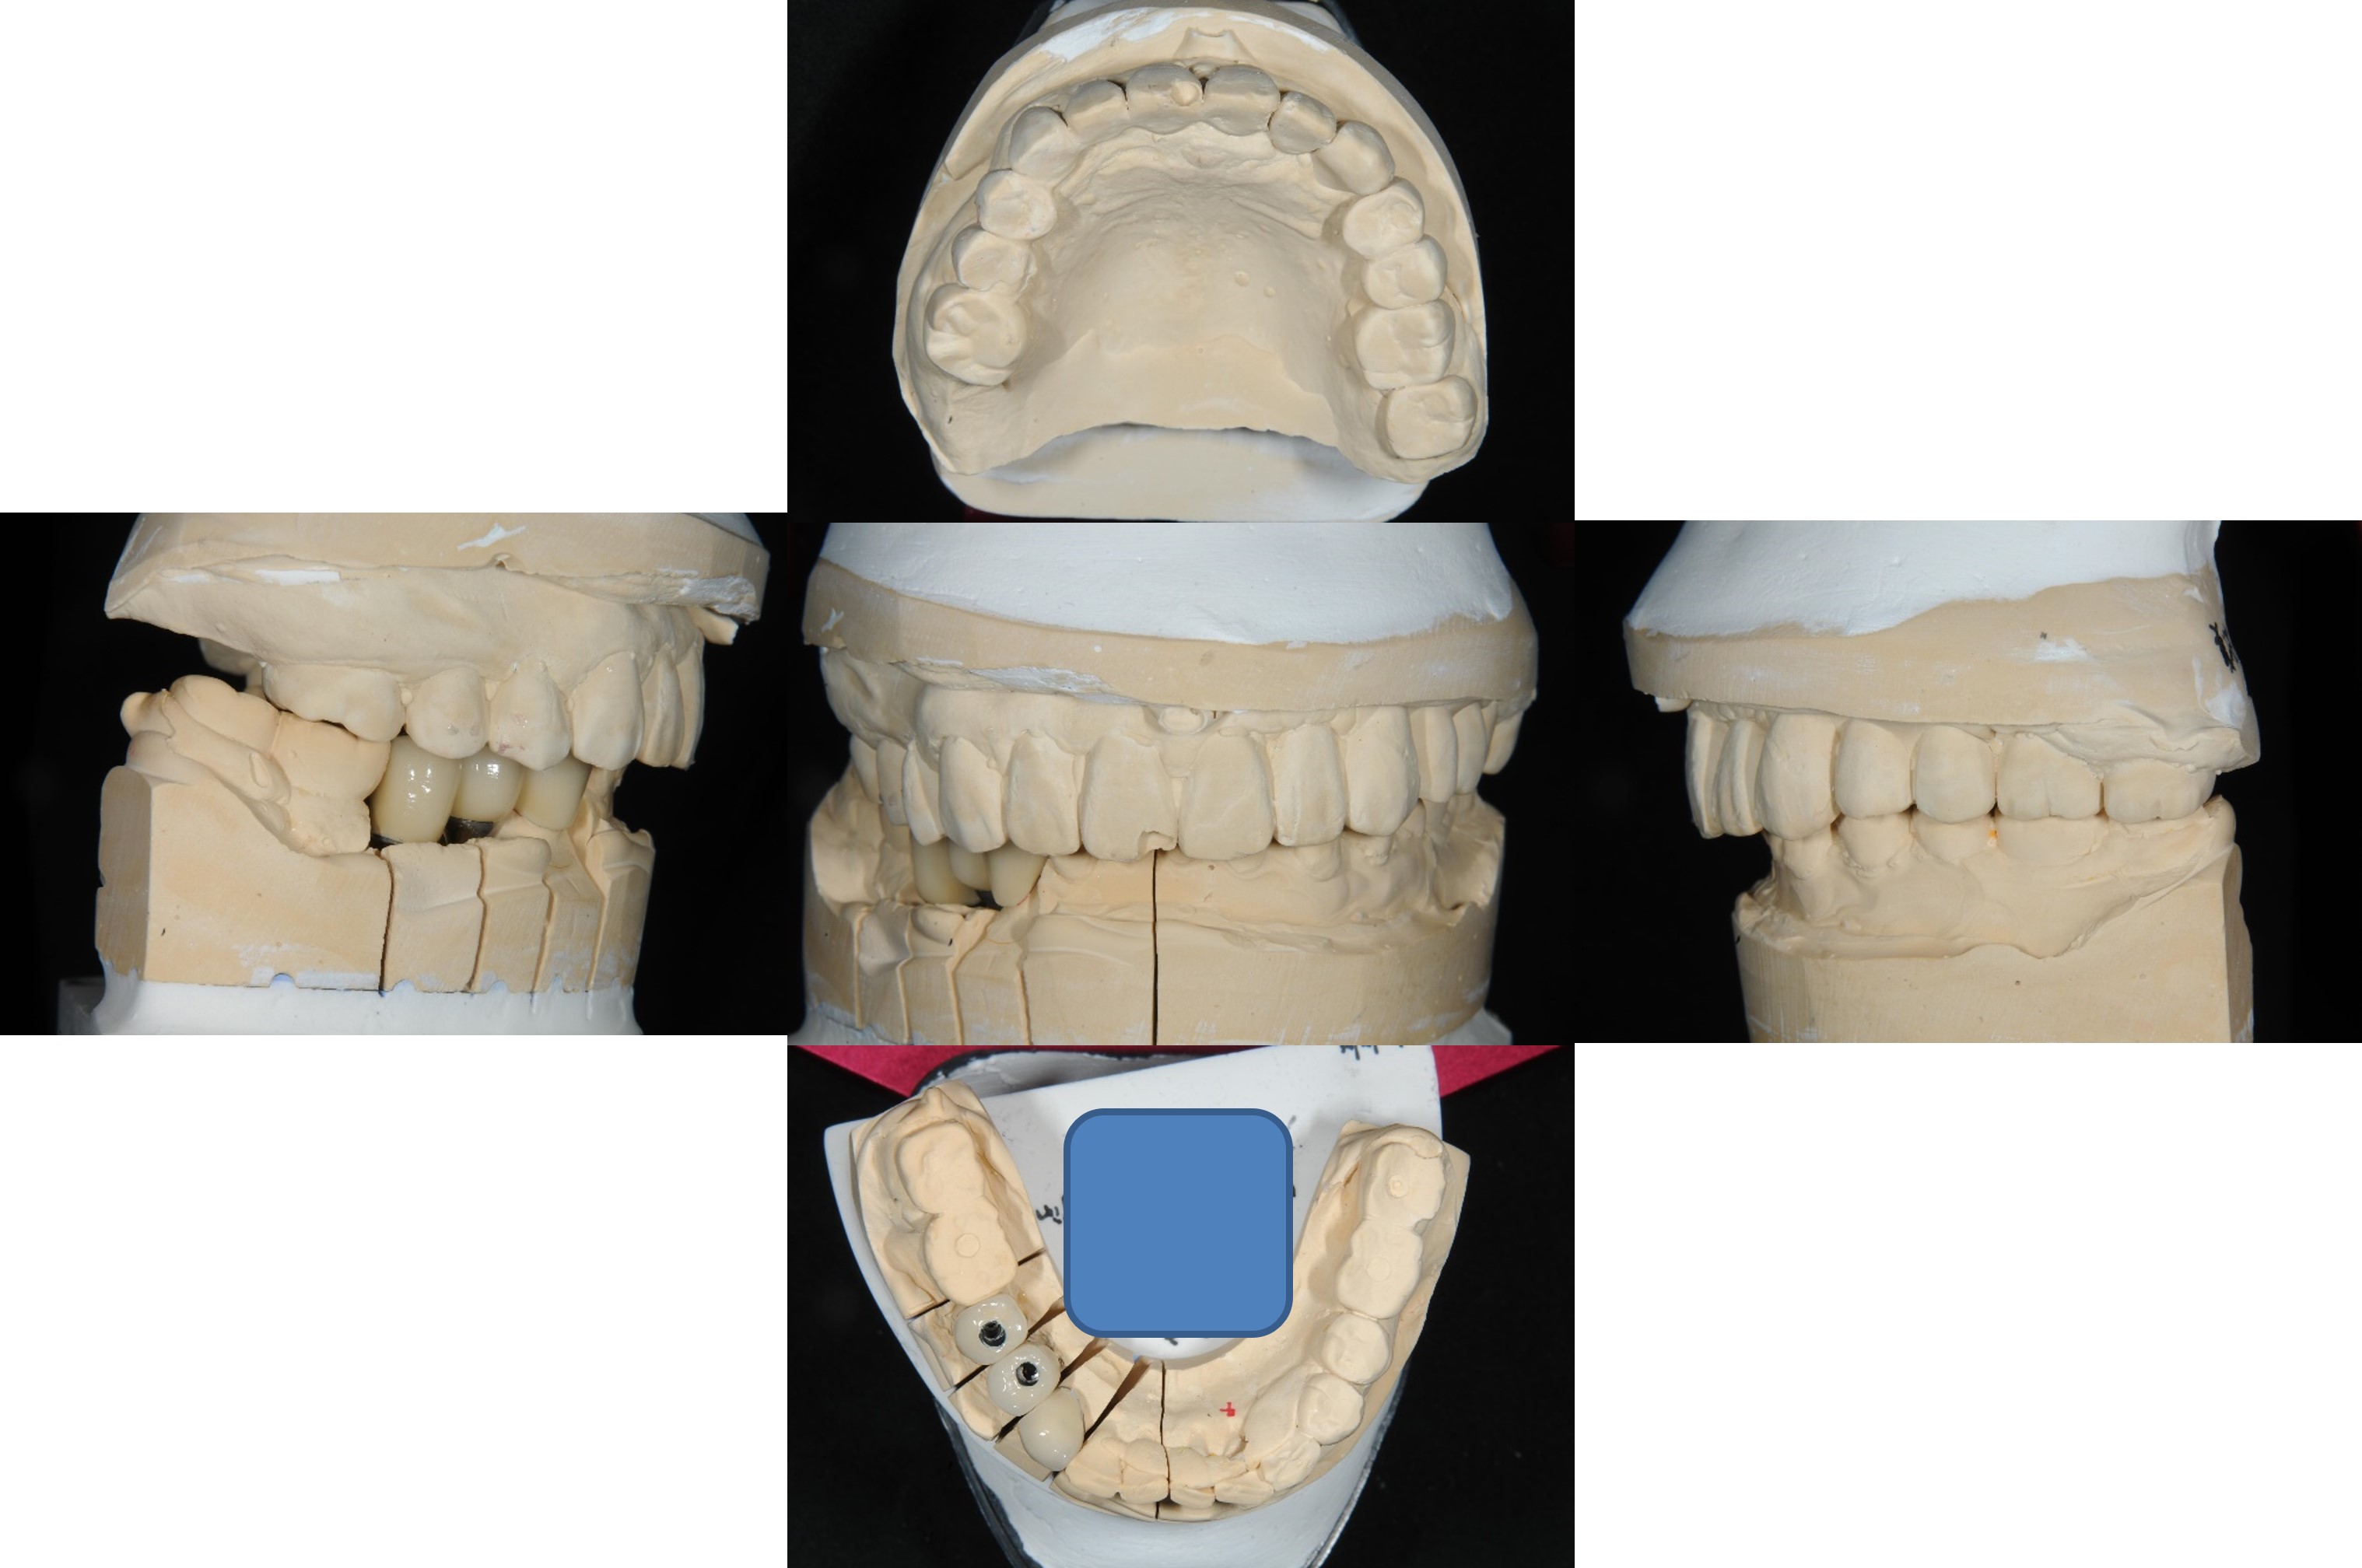

上面弓與咬合器

咬合器上製作假牙